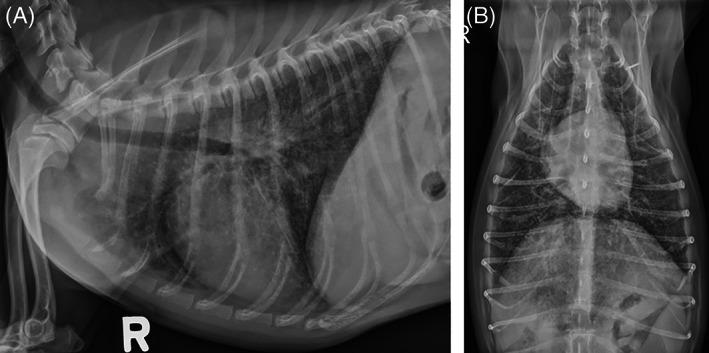

Sibling female and male Chihuahuas were evaluated for a 9-month history of tachypnea that failed to respond to fenbendazole, doxycycline, amoxicillin-clavulanate, and prednisone. Physical examination identified tachypnea, hyperpnea, and harsh bronchovesicular lung sounds. Fundic examination disclosed diffuse chorioretinitis, manifested as multifocal chorioretinal granulomas in the female dog and occasional chorioretinal scars in the male dog. Thoracic radiographs indicated moderate to severe interstitial to broncho-interstitial infiltrates in both dogs. Serum and urine antigen and antibody testing in the female dog failed to identify infectious agents, but cytologic assessment of hepatic lymph node, liver, and splenic aspirates identified Pneumocystis trophozoites. Infection was confirmed in both dogs by 28S rRNA PCR sequencing from multiple tissue samples. The female dog responded well to trimethoprim-sulfamethoxazole, but the male dog was euthanized because of liver failure, presumably related to antimicrobial treatment.

两只雌性和雄性吉娃娃犬因呼吸急促就诊,病史 9 个月,曾接受芬苯达唑、多西环素、阿莫西林克拉维酸和泼尼松治疗,但未见改善。体格检查发现呼吸急促、过度通气和粗湿啰音。眼底检查显示弥漫性脉络膜炎,表现为雌性犬的多发性脉络膜视网膜肉芽肿和雄性犬偶尔的脉络膜视网膜瘢痕。胸部 X 线片显示两只犬均存在中重度间质性至支气管间质性浸润。雌性犬的血清和尿液抗原及抗体检测未能识别出病原体,但对肝门淋巴结、肝脏和脾脏抽吸物的细胞学评估发现了卡氏肺孢子虫滋养体。通过对多个组织样本的 28S rRNA PCR 测序,在两只犬中均证实了感染。雌性犬对甲氧苄啶-磺胺甲噁唑反应良好,但因肝功能衰竭,雄性犬被安乐死,可能与抗菌药物治疗有关。